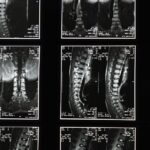

Lors du suivi, plusieurs outils médicaux peuvent être utilisés pour évaluer l’état des disques intervertébraux. Des imageries médicales comme les IRM ou les radiographies peuvent fournir des informations précieuses sur l’état des disques et des vertèbres environnantes. Grâce à ces examens, les professionnels de santé peuvent identifier des problèmes tels que la protrusion discale ou l’arthrose interapophysaire, permettant ainsi un diagnostic précis et des décisions éclairées sur le plan de traitement.